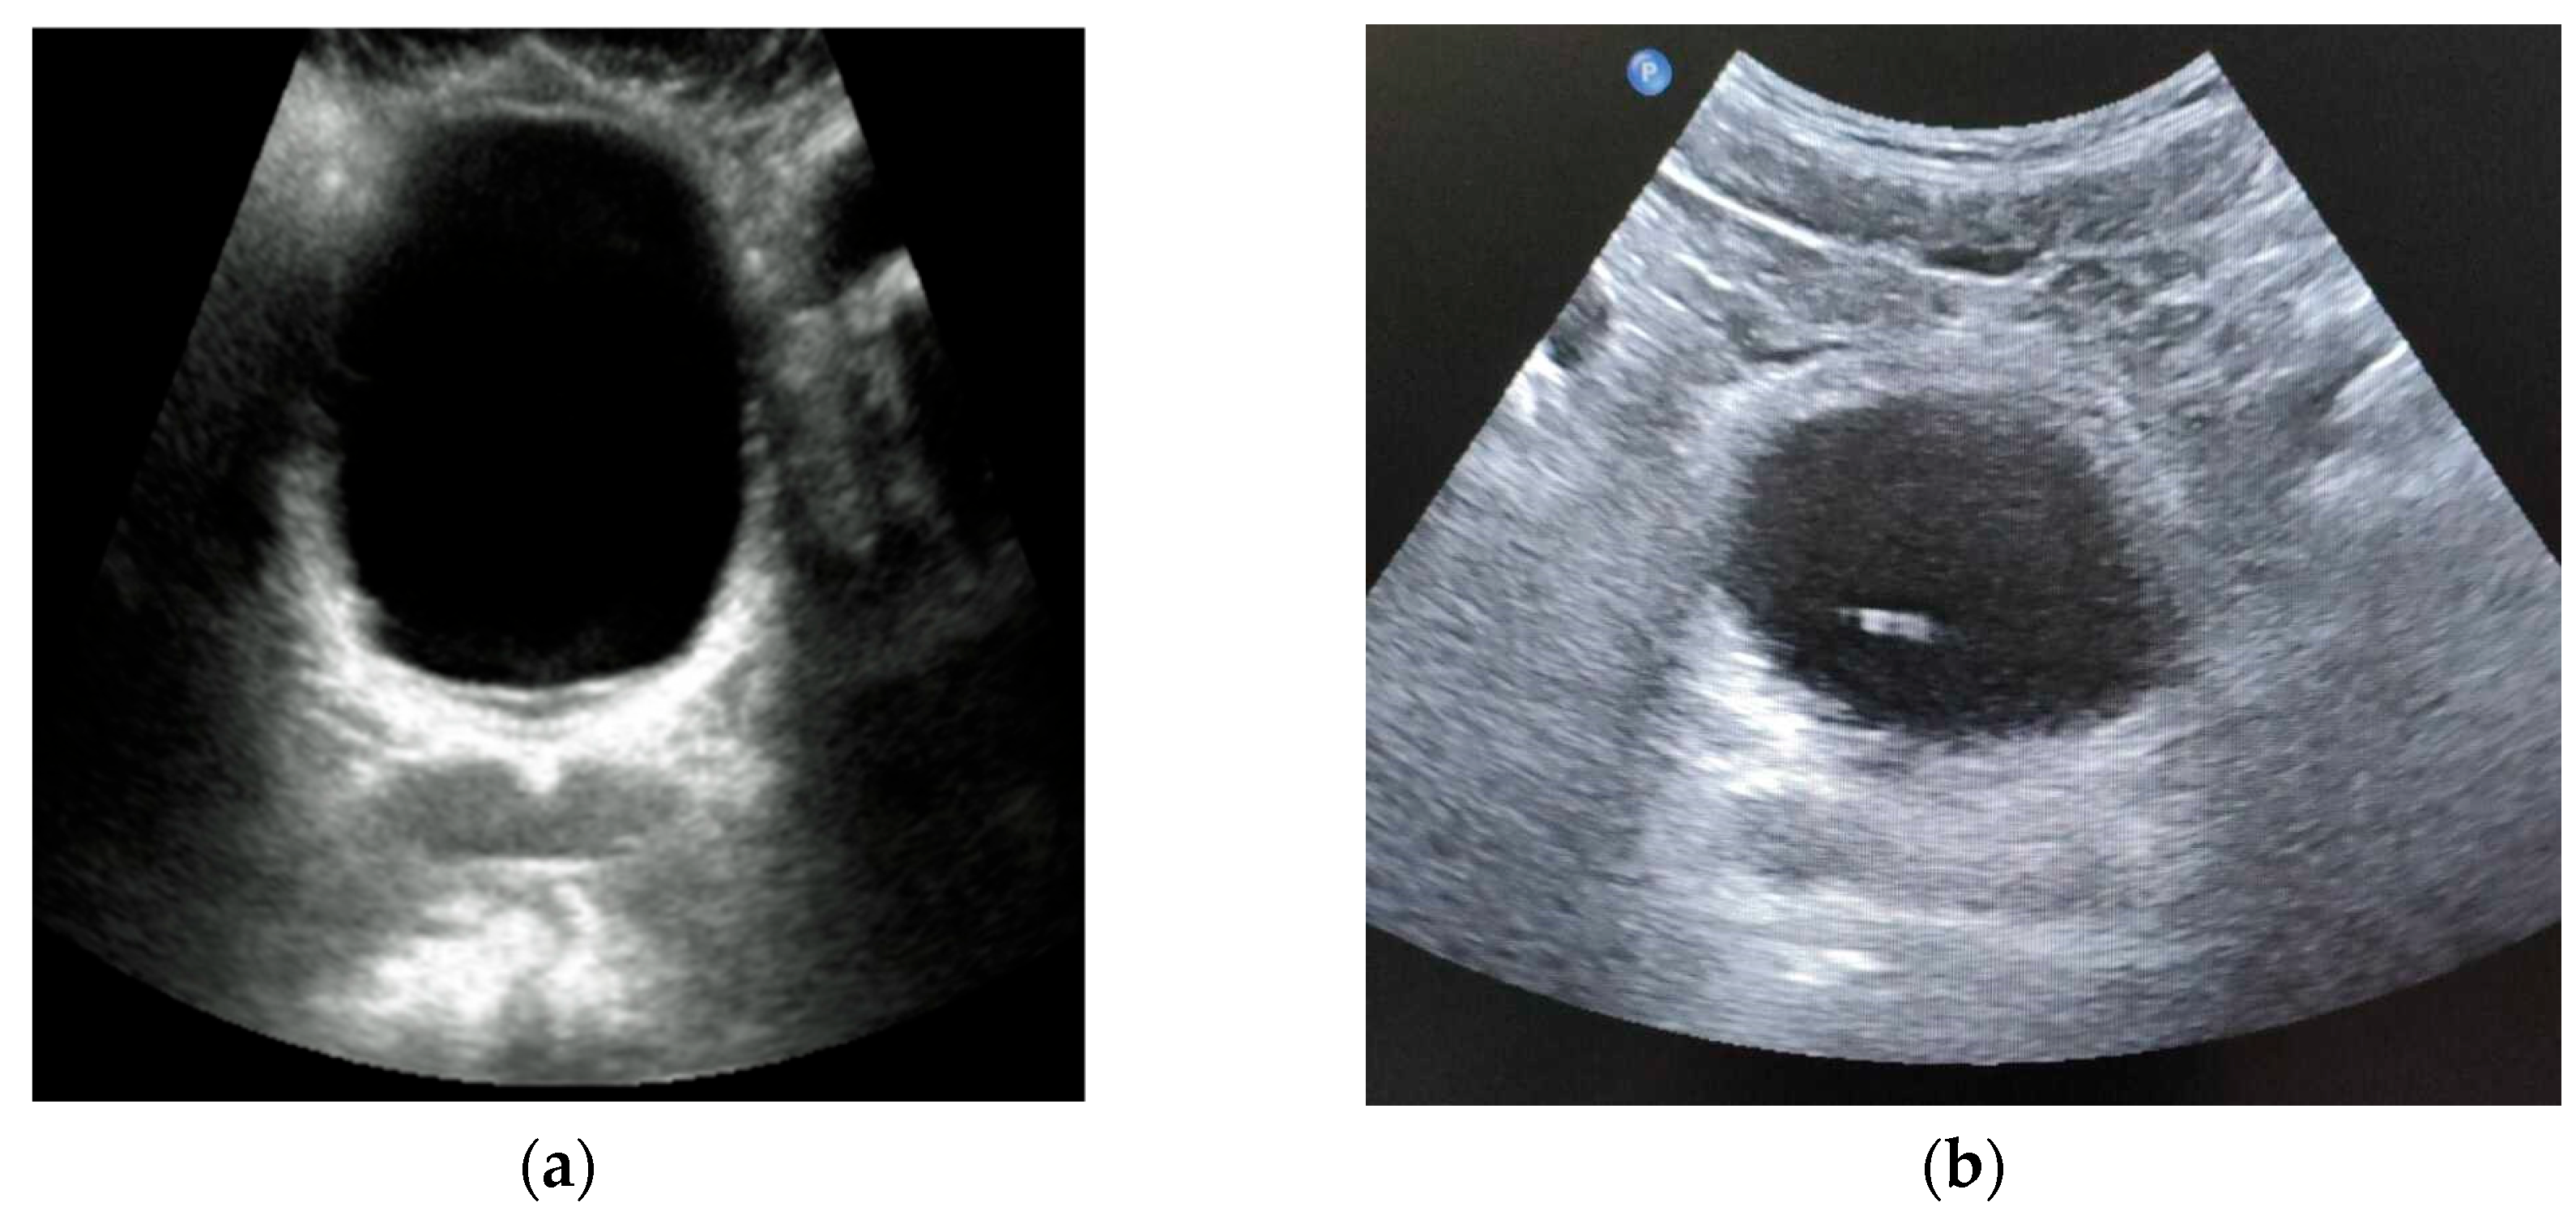

- Zhang, X.; Husmann, D.A.; Mynderse, L.A.; Alizad, A.; Fatemi, M. Non-invasive assessment of urinary bladder compliance using ultrasound: first validation study based on clinical urodynamic study. Annals of Translational Medicine 2021, 9(7), 547–555. [Google Scholar] [CrossRef] [PubMed]